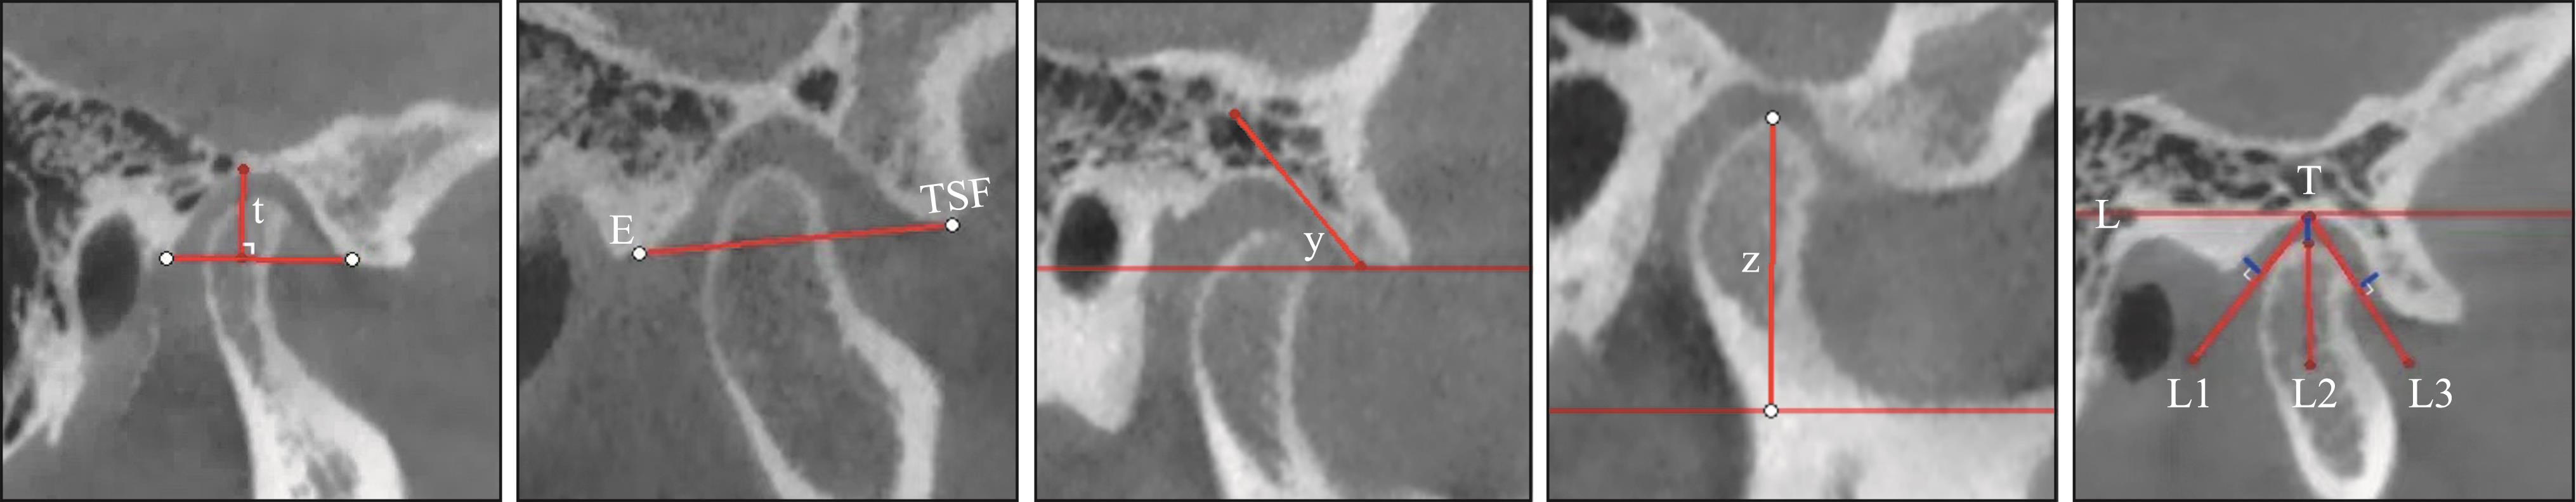

李晓星, 马博文, 徐鑫宇, 等. 伴偏侧咀嚼颞下颌关节骨关节炎患者1年随访的CBCT研究[J]. 口腔颌面修复学杂志, 2025, 26(1): 42-49.

|

Li XX, Ma BW, Xu XY, et al. CBCT study of patients with temporomandibular joint osteoarthritis accompanied by lateral chewing for 1 year follow-up[J]. Chin J Prosthodont, 2025, 26(1): 42-49.